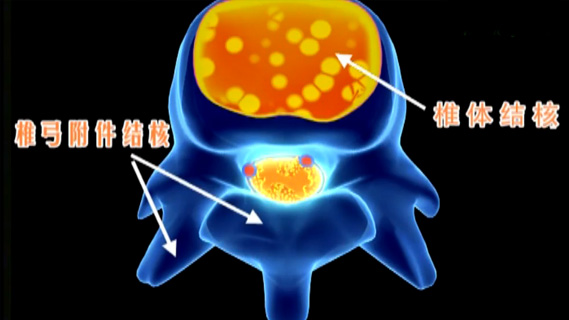

椎弓结核_椎弓结核的症状_椎弓结核的原因

569x320 - 43KB - JPEG